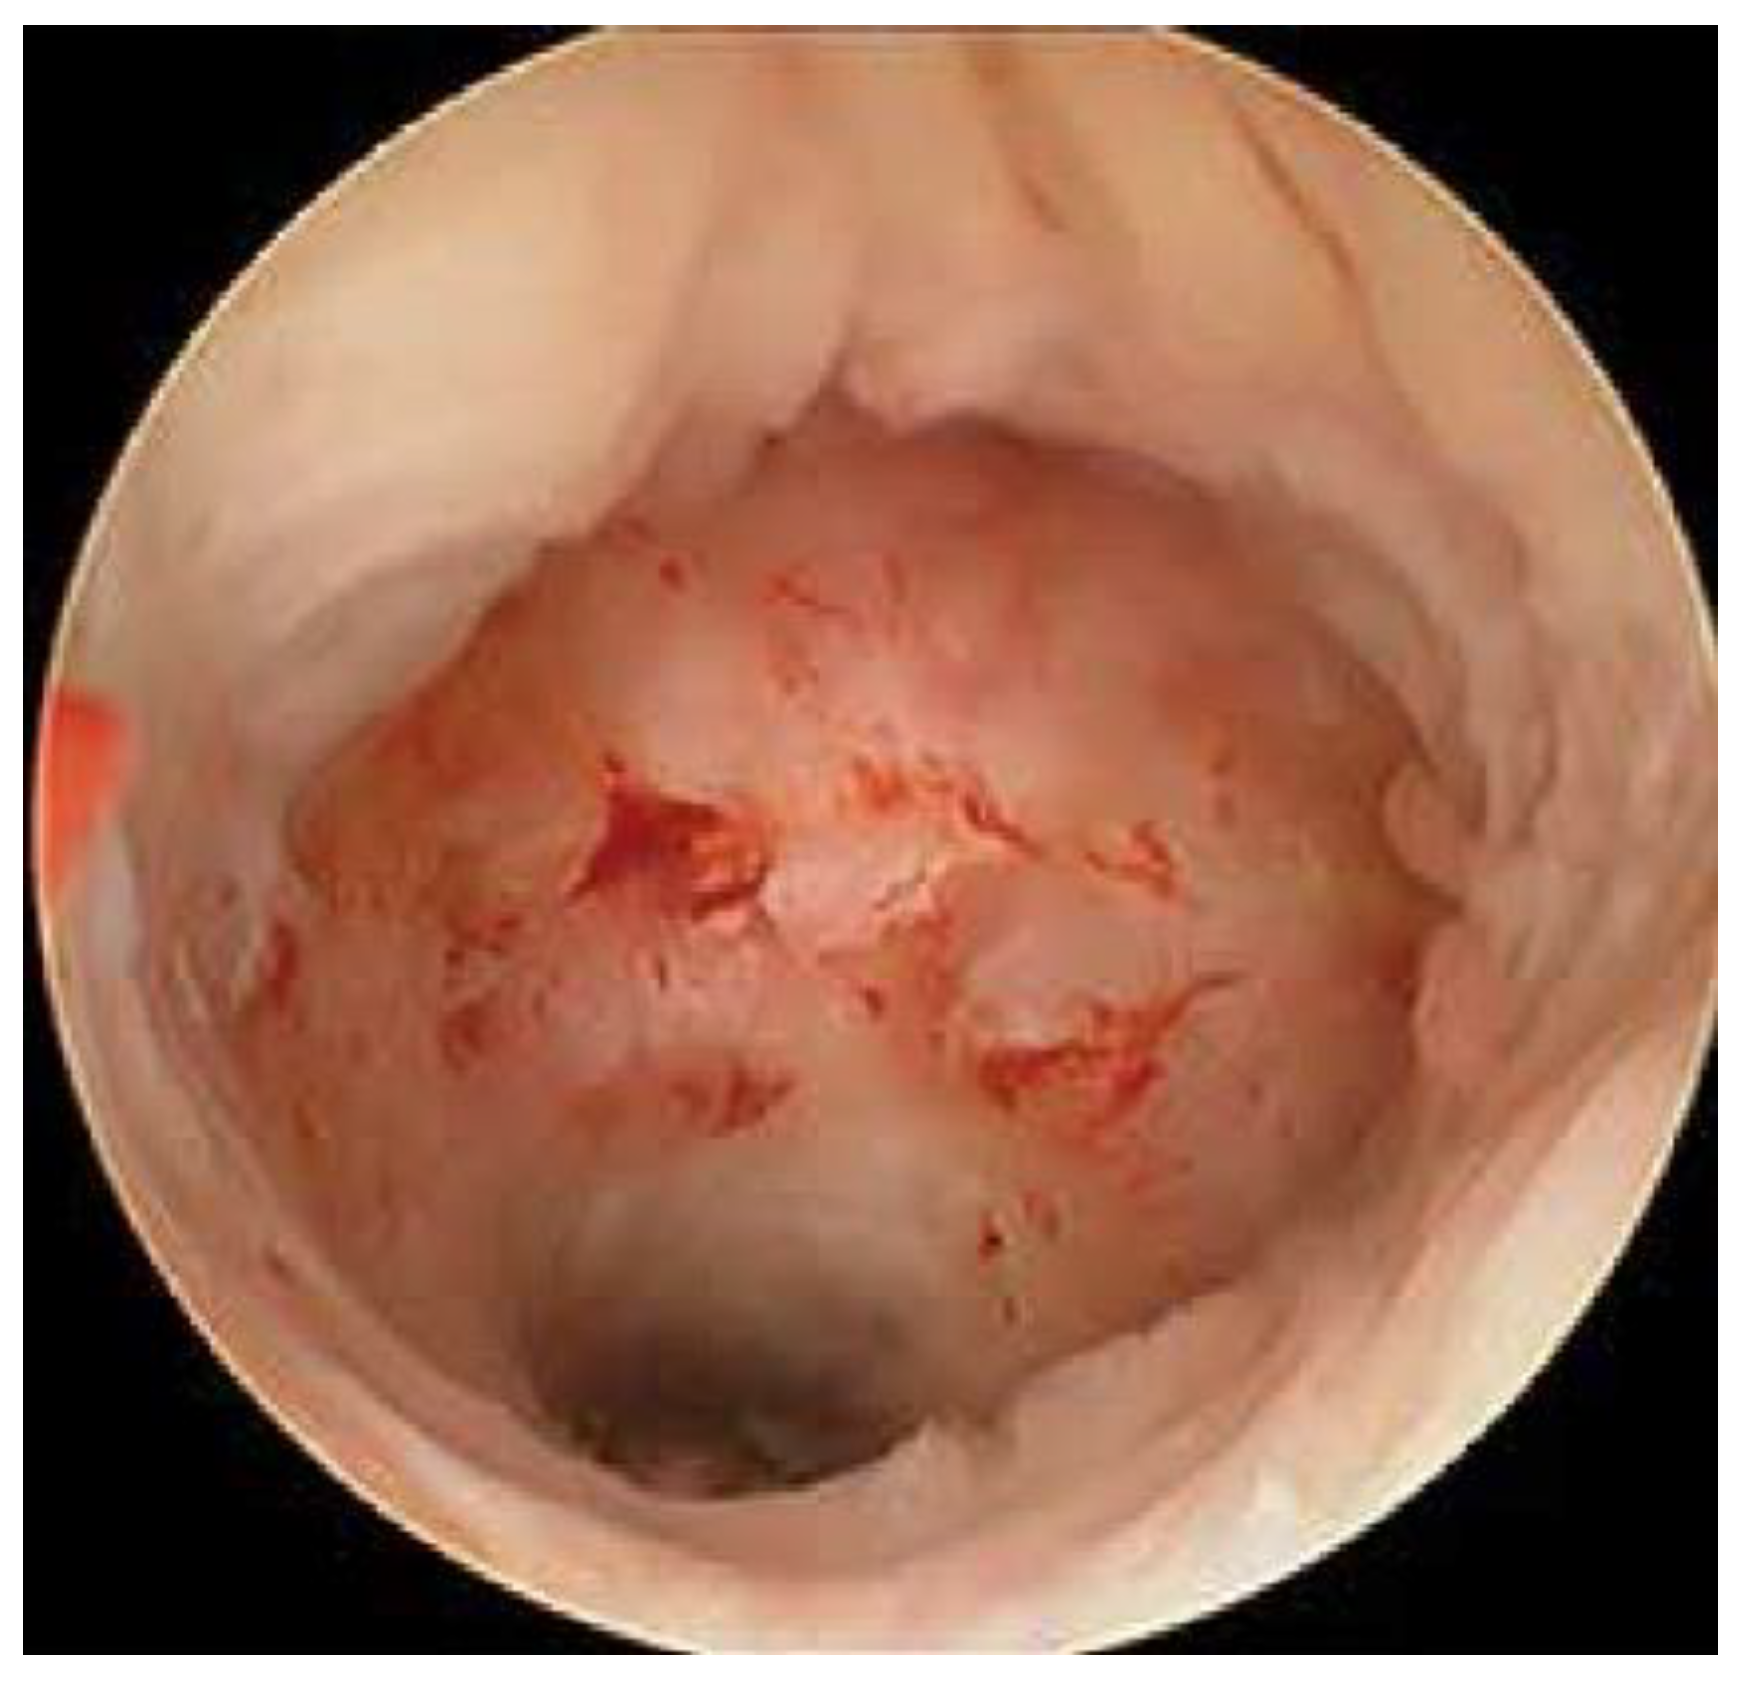

| Surgical Approach of Repair | Hysteroscopy only | 1 | 3.7% |

| Laparoscopy and hysteroscopy | 23 | 85.2% | |

| Hysterectomy | 3 | 11.1% | |